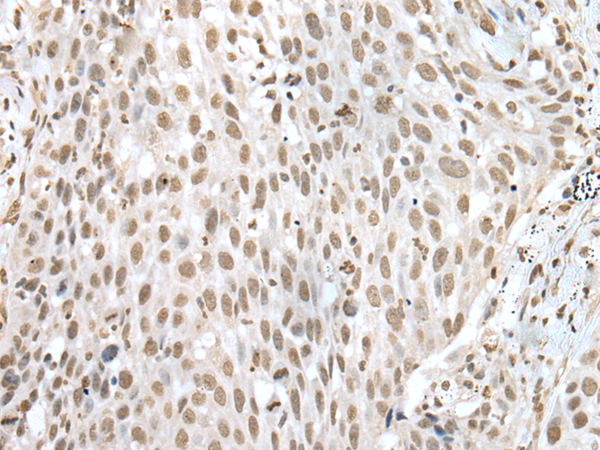

ELISA, IHC

IHC positive control:

Human lung cancer and human gastric cancer

IHC Recommend dilution:

25-100